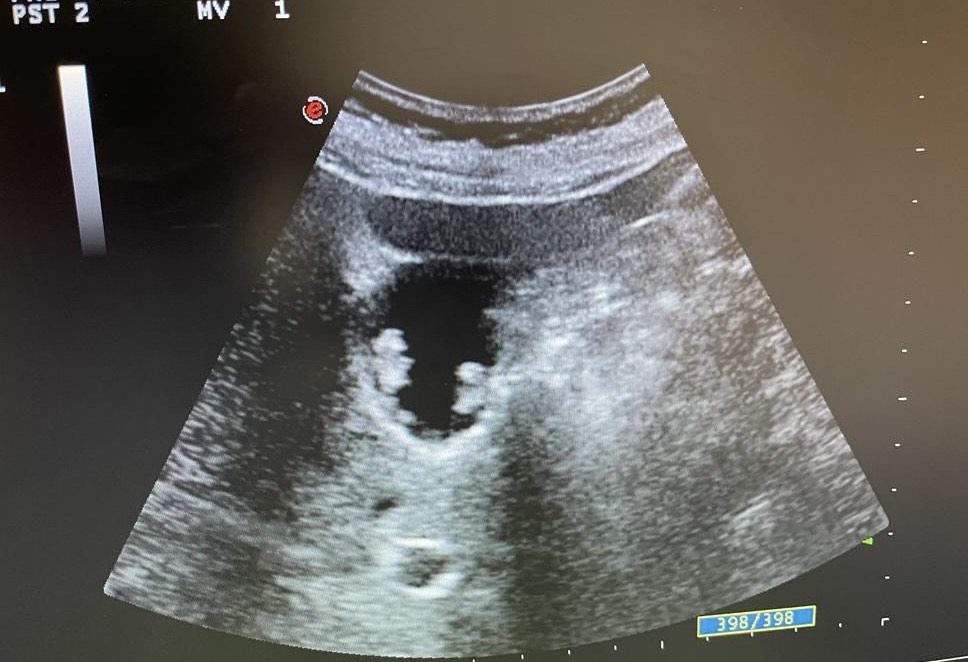

Mentalmente describí las lesiones,  se trata de lesiones múltiples hiperecogénicas  y adheridas a la pared vesicular y que no producen sombra posterior.

Confirmé que no se trataba de colelitiasis sino que en mi opinión eran múltiples pólipos vesiculares y alguno de ellos cercano a 1 cm de diámetro, sin poder descartar malignidad con la ecografía, por lo que solicité un TC abdominal que informó de un único pólipo vesicular de 6 mm.

Desde la consulta de cirugía se solicitó ecografía reglada y control en 6 meses que informó de múltiples engrosamientos nodulares en relación con pólipos (más de 10), los de mayor tamaño alcanzan 9 mm de grosor máximo. Alitiasica.